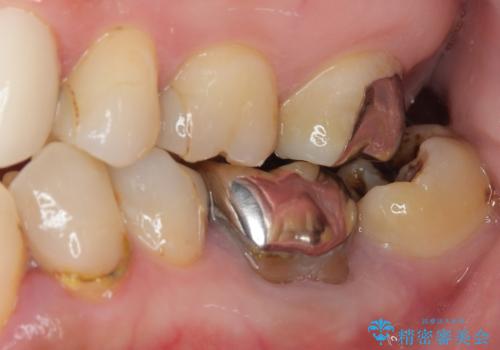

下顎大臼歯の再根管治療とオールセラミッククラウンによる補綴治療

- 10年以上前に治療した銀歯をやり替え希望で来院された患者様です。

噛んだ時に少し違和感があり、レントゲン上で根尖病変が確認できるため再根管治療を行いました。

根管治療後は、ファイバーコアによる土台と、オールセラミッククラウンによる補綴治療を行いました。

なお、最後方臼歯が手前に傾いていることで汚れがたまりやすい形態を改善するための矯正治療も提案しましたが、希望されなかったためそのまま補綴治療を行っています。